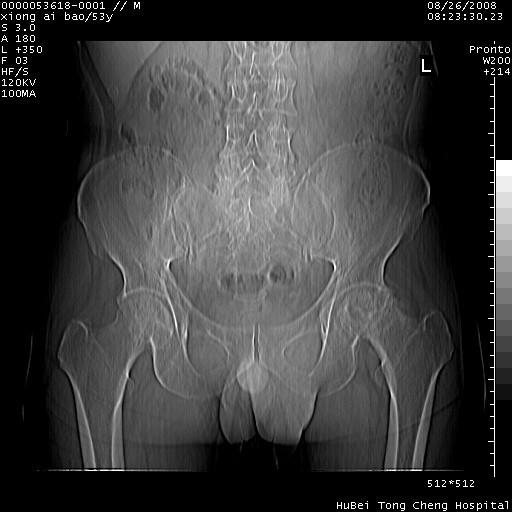

标题: CT15583:M,53Y。请老师指教分析骨盆及其他病变。 [打印本页]

标题: CT15583:M,53Y。请老师指教分析骨盆及其他病变。

股骨头坏死/腹股沟疝。

双侧股骨头无菌坏死,左侧腹股沟斜疝。

非常典型病例,双侧股骨头坏死伴双髋关节周围软组织肿胀,左腹股沟疝。

支持双侧股骨头无菌坏死,左侧腹股沟斜疝。

双侧股骨头坏死伴双髋关节周围软组织肿胀,左腹股沟疝。

双侧骨股头无菌性坏死,左侧腹股沟疝

双侧髋关节肿胀明显,感觉还不能排除结核。

考虑双侧髋关节结核,左侧腹股沟疝